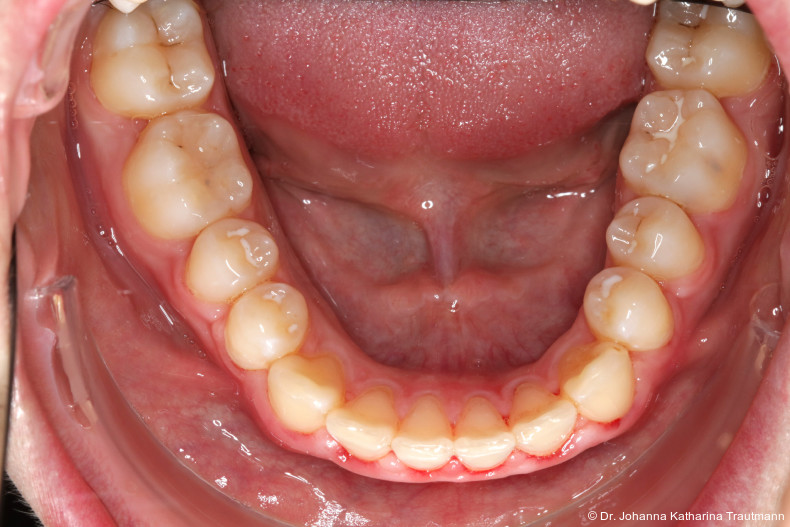

Im Rahmen der Multibrackettherapie wurde bewusst der Zahn 13 aus dem Hauptnivellie rungsbogen ausgelassen, um Kippungen und Asymmetrien im Zahnbogen zu vermeiden. Der Zahn 23 wurde locker mit einer Distanz ligatur angebunden, um eine weitere Bewegung nach vestibulär zu erreichen. Auf einem 0.019" x 0.025" Stahlbogen erfolgte anschlie ßend mittels Umgehungsbiegung sowie eines Overlaybogens (0.014" NiTi) die Integration des Zahnes 13 in den Zahnbogen. Die Zwischendiagnostik nach einem Jahr festsitzender Behandlung zeigte eine gelungene Bisshebung bei guter Nivellierung des Okklusionsplanums und orthoaxialer Einstellung der Frontzähne. Die Zahnbögen präsentierten sich harmonisch ausgeformt, es zeigte sich jedoch eine verbleibende Torqueproblematik an bei den Oberkiefereckzähnen. Nach Freilegung und Einstellung verlagerter Eckzähne ist eine korrekte Torque und Angulationssteuerung häufig eine Herausforderung. Während vestibulär verlagerte Zähne zu gingivalen Rezessionen neigen, behalten palatinal verlagerte Zähne oft ihre palatinale Wurzelstellung bei.13, 14 Die genutzte MBTPrescription der Brackets bietet die Möglichkeit, zwischen +7°, 0° und –7° Torque zu wählen.15 In einem 0.022" System ist bei Verwendung eines 0.019" x 0.025" Bogens jedoch mit einem Torqueverlust von etwa 10° zu rechnen.16

Eine rein klassische „Hochnivellierung“ führt daher zu keiner aus reichenden Torqueübertragung. Alternativ kann ein individualisiert eingebogener Einzelzahntorque eingesetzt werden, um diesen Verlust auszugleichen. Zum Zeitpunkt der Zwischendiagnostik bestand weiterhin eine asymmetrische Bisslage sowie ein vergrößerter Overjet, die beide im weiteren Verlauf mithilfe intermaxillärer Gummizüge korrigiert wurden. Bereits in dieser Phase erfolgte eine Rück sprache mit der Abteilung für Präventive Zahnmedizin, Parodontologie und Kariologie, um eine optimale Ausgangssituation für den späteren odontoplastischen Umbau des Zahnes 22 zu schaffen. Eine präzise kieferorthopädische Einstellung kann die restaurative In vasivität deutlich reduzieren und die Gewebe symmetrie, einschließlich Papillen und Gin giva verlauf, positiv beeinflussen.17, 18 Optimalerweise werden Funktion und Ästhetik vor Entfernung der Multibracketapparatur interdisziplinär abgestimmt, um sowohl aus kieferorthopädischer als auch konservierender Sicht das bestmögliche Ergebnis zu erzielen. Auch das Terminmanagement sollte frühzeitig abgestimmt werden, um eine zügige Rehabilitation zu gewährleisten.

Das zunächst geplante Retentionskonzept aus herausnehmbarer und festsitzender Apparatur konnte leider nicht vollständig umgesetzt werden, da der Patient eine festsitzende Retention nicht wünschte. Die DVP ermöglichte zwar eine gute sagittale Retention, dennoch kam es zu einem Rezidiv der Zähne 33 und 43, die sich zum Behand lungsende mesiorotiert zeigten. Auch die Kongruenz der Mittellinien sowie die Korrektur der Torqueproblematik der Oberkiefereckzähne konnten nicht vollständig erreicht werden.